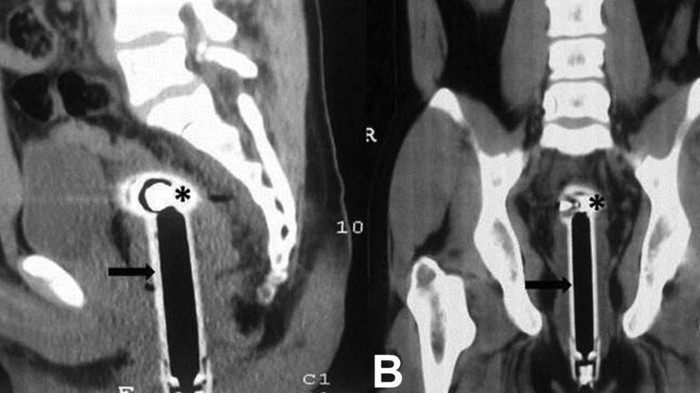

Hasil pemindaian menunjukkan ada kepala shower terjebak di anusnya, namun tidak memicu kerusakan organ. Dokter memberikan anestesi atau bius umum untuk bisa mengeluarkan benda itu dari anus si pria.